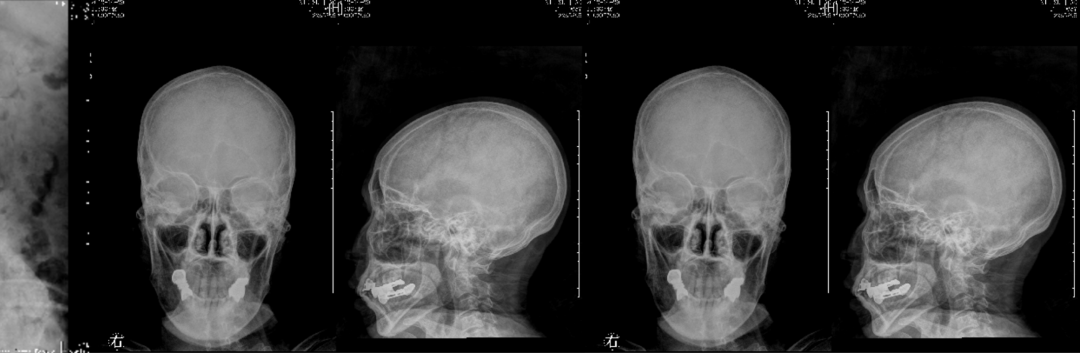

X线检查:L2压缩性骨折椎体骨质疏松,头颅未见异常。

X线检查:胸腰椎多发压缩性骨折伴骨质疏松。